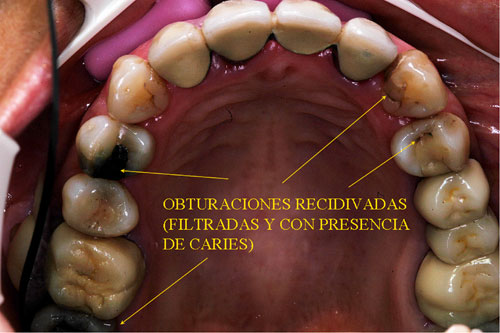

RESUMEN Mostración del Protocolo en R. O. y su desarrollo clínico. DESARROLLO Quienes realizamos Rehabilitación Bucal Integral desde muchos años atrás, siempre hemos buscado un protocolo coherente que nos permitiera ordenar el pensamiento cuando nos encontramos con aquellos caóticos casos donde marearse en la resolución es fácil y frecuente. PROTOCOLO DE ALONSO Sintéticamente consiste en otorgar al Sistema en primer término: Desoclusión en Lateralidades y Propulsiva de los sectores posteriores, mediante la construcción de la Guía Anterior tanto en los Provisorios como en los Definitivos, basados en el Encerado de Diagnóstico. PROTOCOLO PRÁCTICO (BASADO EN D.A.T.O.) Diagnóstico: clínico, radiográfico (donde no es necesario extenderse) y de laboratorio, donde mediante un encerado diagnóstico y otro de trabajo, conoceremos la fiel réplica de la boca del paciente antes de destruirse y los medios para reconstruirla basados en los procedimientos que podemos realizar en la cera. PRESENTACIÓN DEL CASO Se presenta la paciente derivada por un compañero a fin de consultar acerca de un primer molar superior izquierdo, a quien el Periodoncista aconsejaba realizar una radectomía debido a la pérdida ósea distal que dicha raíz presentaba. Dicha observación hace que decidamos tomar una actitud más conservadora, explicando al enfermo las razónes etiológicas de la pérdida ósea, y aconsejando quitar dicha funda para colocar una provisional morfológicamente correcta, y simultáneamente re-endodonciar y realizar la terapia básica periodontal. Visión Global del Caso Se observa a la inspección clínica y radiográfica, varios puentes fijos filtrados, como así también amalgamas de plata recidivadas. Inversión de la Curva de Wilson.(2º Elemento a nuestro alcance para obtener Desoclusión Se procede entonces luego de realizar los correspondientes modelos de yeso mediante impresiones precisas de alginato con cubetas Rim Lock, a tomar un registro cráneo maxilar mediante un arco facial estático (Artex) que nos permita montar el modelo superior respecto del Plano de Frankfurt con el punto Gnation de referencia. Luego, haciendo uso de las Laminillas de Long , (buscar referencias en el libro del Dr. Alonso o bien en múltiples publicaciones personales en Gaceta Dental o Maxillaris, como así también en mi propia web: en los artículos : RELACIÓN CÉNTRICA o AJUSTE OCLUSAL, BASES FILOSÓFICAS DE UNA OCLUSIÓN ORGÁNICA), (www.dracuna.com o www.oclusión.es,) . Procedemos a obtener el Registro Inter Maxilar de OCLUSIÓN EN RELACIÓN CÉNTRICA, mediante el cual, montamos el modelo inferior respecto del superior. Montamos así, en un Artex totalmente ajustable, pués no contábamos en ese momento con ningún semiajustable disponible,(ya que estaban todos ocupados), ajustando el Ángulo de Bennet y la Inclinación de la Trayectoria Condílea en gradaciones personalizadas mediante registros de Propulsión y Lateralidades). Procedemos entonces al estudio de los modelos. DIAGNÓSTICO GENERAL Disfunción oral generalizada, provocada por alteraciones en la Oclusión, en la Operatoria Dental, en la Endodoncia, en la Periodoncia y en la Prótesis realizada en esta boca a través de los años. Filtración generalizada de fundas. DIAGNÓSTICO PROTÉTICO OCLUSAL Carencia de guía canina. Carencia de alineación tridimensional en guía anterior. Carencia de curva de Wilson. TRATAMIENTO SUGERIDO 1-Encerado Progresivo de Diagnóstico y Trabajo de Peter K. Thomas. HEMOS OBTENIDO: D.AT.O Hasta aquí, hemos solo observado los elementos de diagnóstico clínicos, radiológicos y de laboratorio, como para comenzar a trabajar. AUTOR: Colaboración: CASO PRESENTADO EN LAS SESIONES CLÍNICAS DEL ILTRE. COLEGIO DE DENTISTAS DE MÁLAGA. Ratificación del Protocolo en Rehabilitación Bucal a pesar de las incidencias propias de cada caso clínico. A propósito de un caso.

Aconsejamos a la paciente realizar un estudio de toda la boca, ya que el molar en cuestión constituía apenas una muestra más de una odontología parcial, iatrogénica, y mal llevada, durante muchos años.

Realizamos fotografías de toda la boca y la correspondiente ortopantomografía apoyada por imágenes de laser visiografía seriada, estudio inicial mínimo necesario para diagnosticar el funcionamiento del SEG.